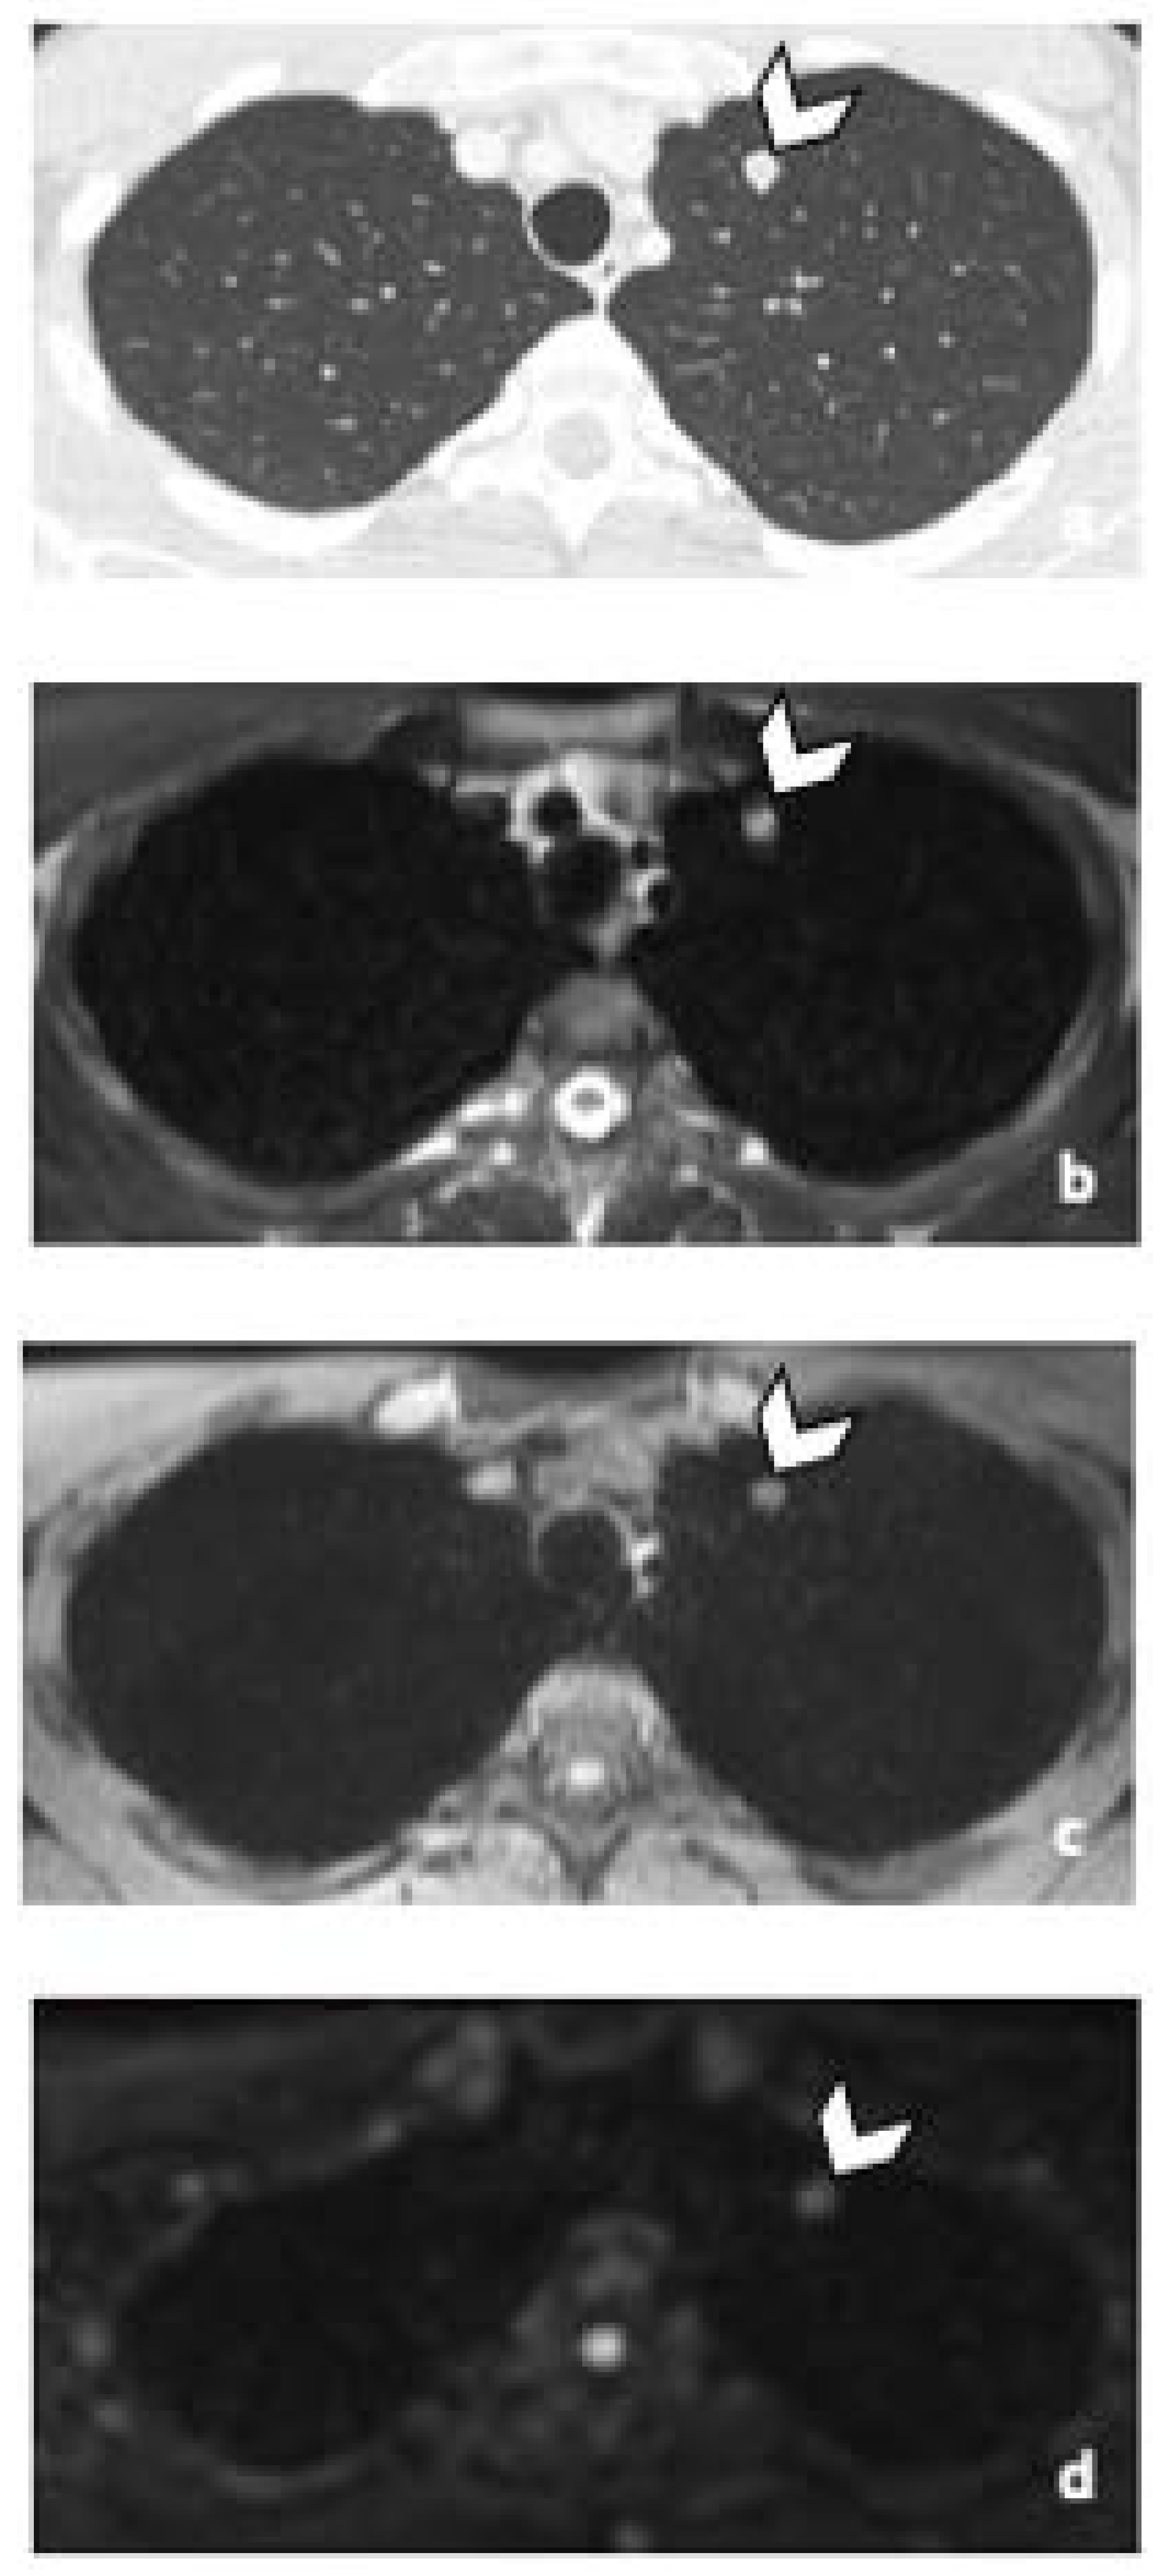

All RPLN patients were detected in both CT and WB-MRI readings by both readers (Figure 1 and Figure 2). Predictive accuracy was 100%, regardless of both, the imaging protocol and the reader. Equivalently, perfect agreement with the reference standard was observed (all AC1 values = 1.00).

Figure 1.

29-year-old man with NSGCC. Axial T2-weighted MR image (a), coronal reformatted 3D T1 GRE Fat-Sat (c) and high b-value DWI (inverted greyscale, b = 1000 s/mm2) (d) of MR images of the whole body and axial CT image after intravenous injection of iodinated contrast agent (Xenetix 350®) and per os contrast opacification (Telebrix Gastro® 5%) (b), showing interaorticocaval enlarged pathological lymph nodes (arrowheads), identified by both readers during MRI and CT readings. The lymphadenopathies show an intermediate to high signal intensity on T2 (a), an heterogenous low and high signal intensity on T1 (c) compatible with histological component of NSGCC and a restricted Diffusion (d). Note the presence of a left supraclavicular lymphadenopathy visible on DWI (d: arrow). Abbreviations: NSGCC: Non-Seminomatous Germ Cell Cancer, 3D: Three Dimensional, T1 GRE: T1 Gradient Echo, DWI: Diffusion Weighted Imaging, MRI: Magnetic Resonance Imaging, CT: Computed Tomography.

Figure 2.

Comparison of WB sequences in a 30-year-old patient with seminoma. Axial T2-weighted (a) and coronal reformatted 3D T1 GRE In Phase (b), 3D T1 GRE Fat Sat (c) and high b-value DWI (inverted greyscale, b = 1000 s/mm2) MR images of the whole body (d). Detection of an enlarged pathological para-aortic lymph node (arrowhead) demonstrating an intermediate signal intensity in T2 (a), a hypointense homogenous signal in T1 (b,c) and a restricted Diffusion (d). In this case, each sequence clearly depicted the retroperitoneal lymph node. Abbreviations: 3D: Three Dimensional, T1 GRE: T1 Gradient Echo, DWI: Diffusion Weighted Imaging.